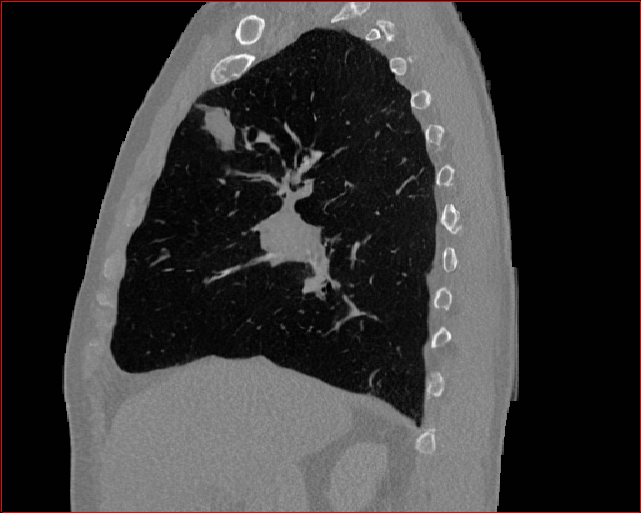

MAISI-v2 Controlnet qualitative Results:

Figure 5 shows qualitative results for MAISI-v2 Controlnet on 5 types of tumors.

Lung Tumor

0.75×0.75×0.60.75\times 0.75\times 0.6

mm

512×512×512512\times 512\times 512

Liver Tumor

0.75×0.75×0.50.75\times 0.75\times 0.5

512×512×768512\times 512\times 768

Panc. Tumor

1×1×11\times 1\times 1

Colon Tumor

0.75×0.75×1.50.75\times 0.75\times 1.5

512×512×256512\times 512\times 256

Bone-Les

1×1×1.31\times 1\times 1.3

512×512×384512\times 512\times 384

Figure 5: MAISI-v2 segmentation-guided results for five types of tumors. We show results for different voxel spacing and volume size to demonstrate the flexibility of MAISI-v2. Different Hounsfield Unit window is used to better show the contrast between tumor and normal tissues.